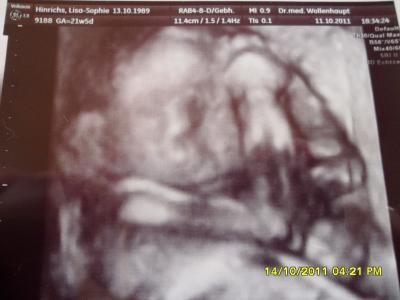

Seid Tagen habe ich das Gefühl das mein kleines Töchterchen mir immerzu unter die rippen tritt dabei meinte mein Arzt am Freitag das die Gebärmutter nun auf Nabelhöhe seih aber man kann auch wenn sie tritt deutlich weit oberhalb des Bauchnabels sehen wie es sich dort ausbeult! =( PS: Sorry das ich zur Zeit so wenig schreibe aber meine Internetverbindung ist hier ziemlich schlecht =( von daher stürzt mir das Internet auch Regelmäßig ab =( aber bin jeden Tag fleißig am Mitlesen =) Meiner Maus geht es soweit gut und auch bei der FD vor 2 Wochen war nichts auffällig =) Sie wiegt jetzt knapp 530 Gramm und ist ca. 29 cm groß =)

Bei mir ist es jetzt die erste SS =) *soooo Glücklich* =) meine kleine dreht sich ständig beim letzten US letzte Woche leg sie mit dem Kopf nach unten und gestern war das Köpfchen wieder oben und heute ist sie wieder mit dem Köpfchen unten =) Und sie ist Mega Aktiv ist das bei dir auch so?